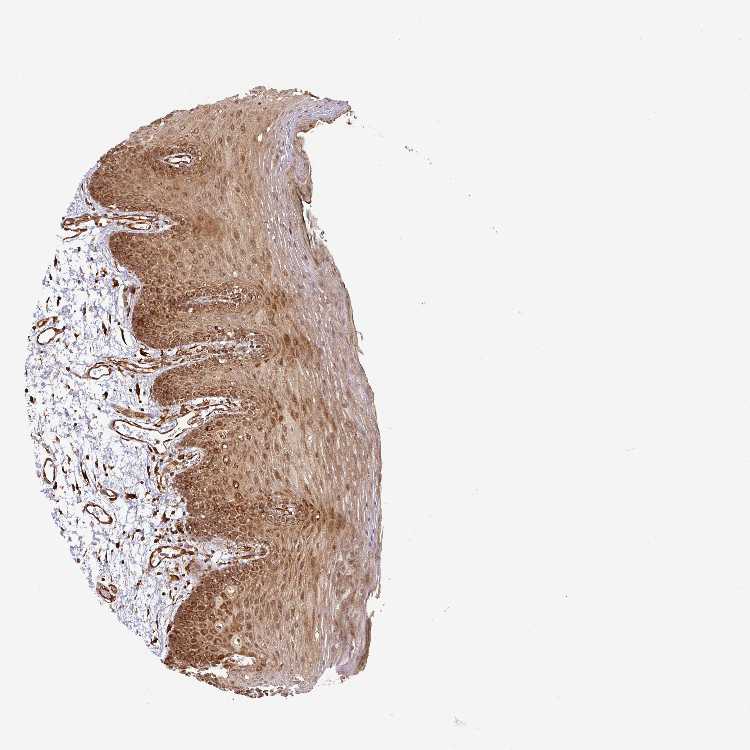

TISSUE PRIMARY DATA ORAL MUCOSA Show tissue menu

ORAL MUCOSA - Antibody stainingi

Antibody staining in the annotated cell types in the current human tissue is reported as not detected, low, medium, or high, based on conventional immunohistochemistry profiling in selected tissues. This score is based on the combination of the staining intensity and fraction of stained cells.

Each image is clickable and will lead to virtual microscopy that enables deeper exploration of all samples and also displays staining intensity scores, fraction scores and subcellular localization as well as patient and tissue information for each sample.

Antibody HPA041082Antibody HPA044227

Squamous epithelial cells HighHigh